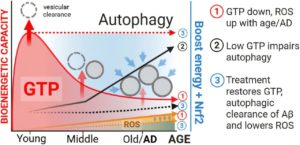

- Mitochondrial dysfunction linked to Alzheimer’s- A4D™

- Brain chemical shifts tied to lifestyle may predict dementia risk- A4D™

- Vitamin B3 and green tea compound help aging brain cells clean up- A4D™

- => Lithium loss ignites Alzheimer’s, but lithium compound can reverse disease- A4D™ <=